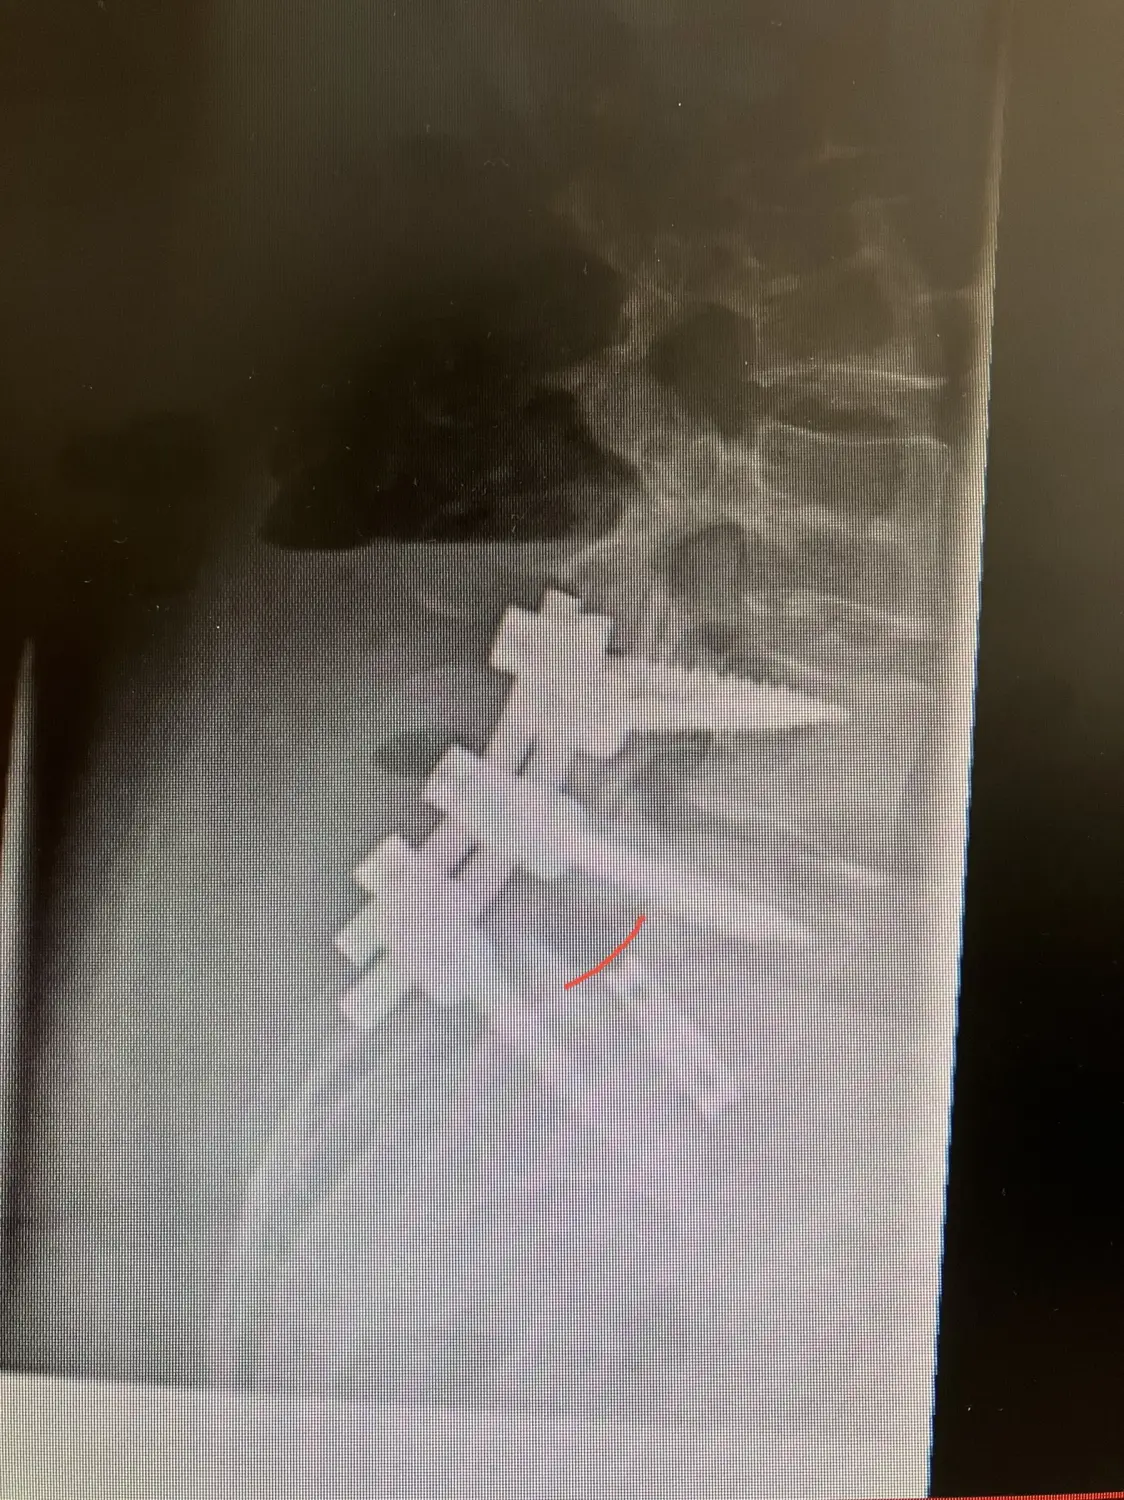

Wenn konservative Maßnahmen keine ausreichende Schmerzlinderung bieten oder neurologische Störungen auftreten, sollte ein chirurgischer Eingriff zur Stabilisierung erwogen werden. Bei dem Eingriff wird auch versucht, die ursprüngliche Form der Wirbelsäule wiederherzustellen. Es gibt verschiedene Operationsverfahren, wie z. B. den Bandscheibenersatz oder die Stabilisierung der Wirbelkörper mit modernen Implantaten. Häufig fürchten Patienten eine Einschränkung der Beweglichkeit nach einer stabilisierenden OP. Durch optimale Auswahl der Segmente sowie kurzstreckige Stabilisierungen ist die gefühlte Bewegungseinschränkung im Alltag zumeist minimal. In einigen Fällen erfahren Patienten nach Stabilisierungsoperationen durch die deutliche Schmerzlinderung nach der Operation sogar eine verbesserte Beweglichkeit. Die Entscheidung für eine Operation hängt von der Schwere des Wirbelgleitens und den individuellen Bedürfnissen des Patienten ab. Nach der Operation können die Patienten in der Regel sofort aufstehen. Ein stabilisierendes Korsett kann in einigen Fällen für die ersten Wochen nach der OP verordnet werden.